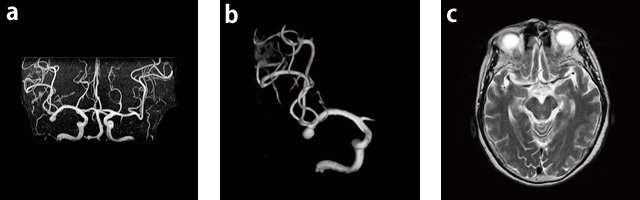

症例3:未破裂動脈瘤右頸部から頭部にかけて痛みがあり,MRIを撮像。

右MCAに7mm大の動脈瘤を認める。

a:MRA,MIP,AP,FOV:170mm,TR/TE:23/6.9,FA:35°

b:VR R-CAG

c:T2WI,AX,FOV:220mm,TR/TE:4800/117,FA:90°,スライス厚:5mm